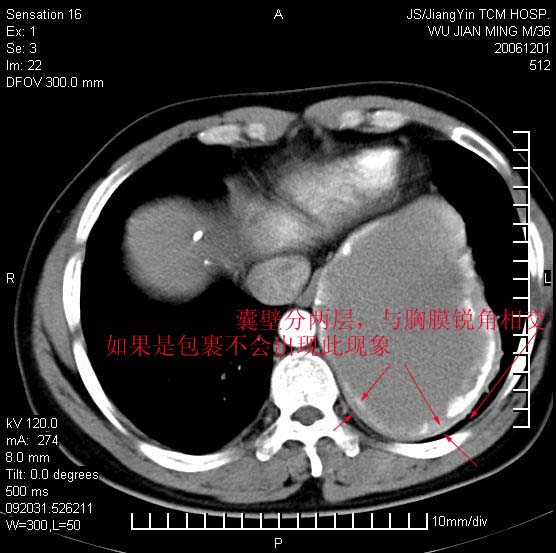

以下是引用dyqct在2006-12-1 21:17:00的发言:[br]左心缘旁及后肋膈窦区见巨大椭圆形混杂密度肿块,周围见大小不等斑片状钙化,内部无强化,周围包膜轻度强化,心脏明显受压变形,即明显占位效应,肿块广基与心包、膈相连。肝、脾内、肝门见多数小结节状钙化影。[br]考虑:1、左心缘旁及后肋膈窦区慢性包裹性胸膜炎(结核性);[br] 2、肝、脾及肝门淋巴结核已钙化。[br]

以下是引用zrs在2006-12-2 17:28:00的发言:[br]肺内、肝脾内虽有钙化,但不支持结核性胸胸膜炎包裹,而支持寄生虫感染![br][br]

以下是引用zyx168在2006-12-2 10:10:00的发言:[br][br]肝脾肺内多发钙化灶